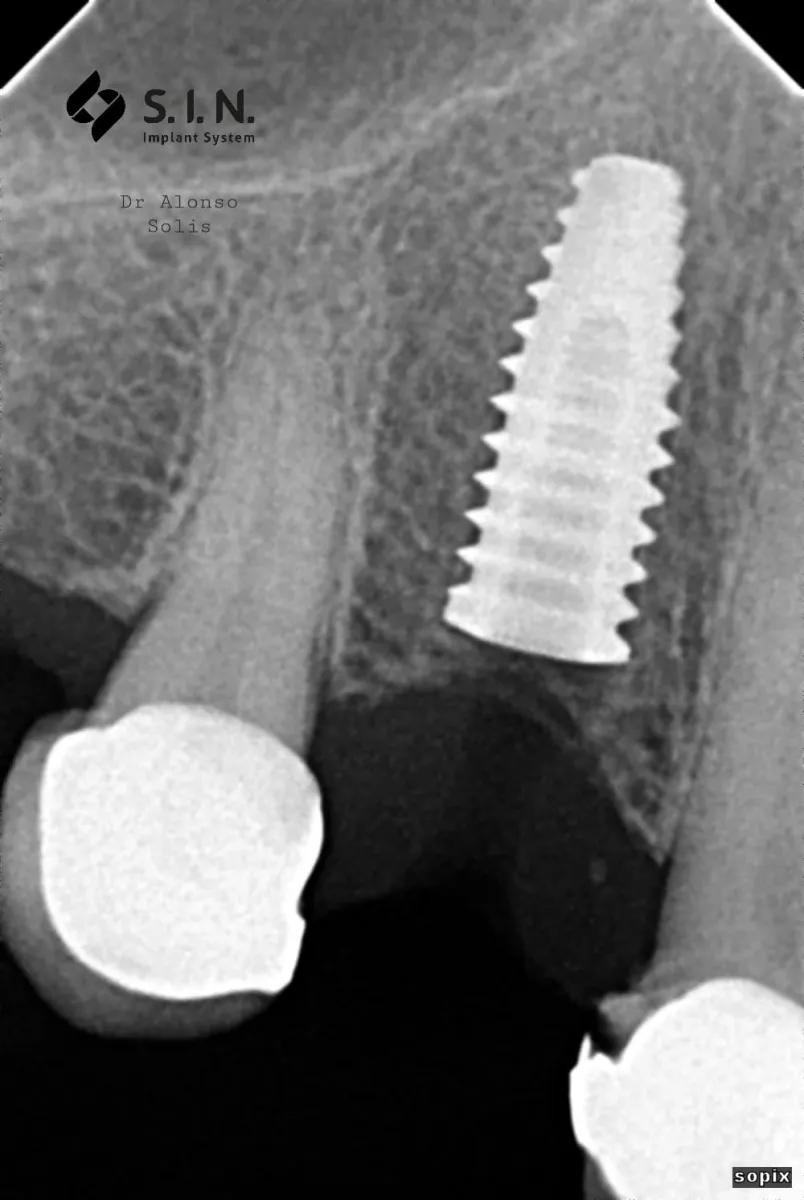

CASO 1

Paciente femenina de 56 años, se presenta a la consulta con puente dental desajustado, con restos alimenticios impactados, se decide realizar un corte de la estructura metálica-porcelana, para conservar piezas restauradas adyacentes, y se coloca un implante dental Marca SIN Implant, realizando provisional para carga inmediata, se espera el proceso de Osteointegración de 4 meses, se observa perfil de emergencia gingival apto, y se procede con la colocación de la corona en Zirconio.